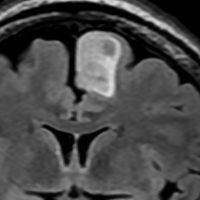

T2-FLAIR mismatch sign (T2とフレアの信号が違うこと)

protoplasmic astrocytomaに特徴的なMRI所見です。T2強調画像(左側)では白く(強い均一な高信号)見えます。でもフレア画像(右側)では白く縁取ったように見えます。びまん性星細胞腫の大きな特徴とされます。内部がとても柔らかいドロドロした腫瘍のこともあります。